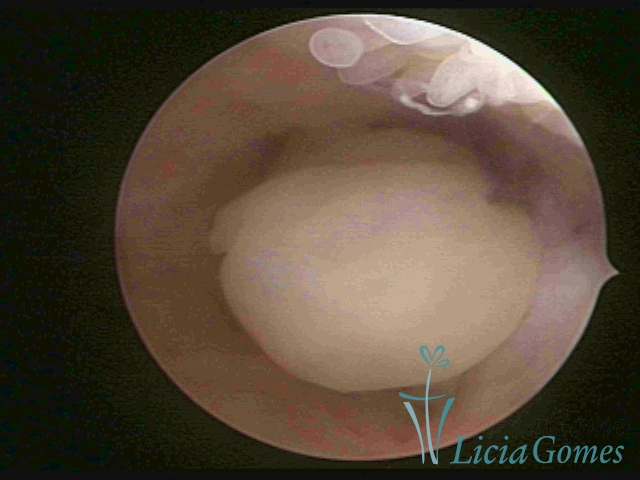

ENDOCERVICAL POLYPS

Benign tumors resulting from the reactive focal proliferation to inflammatory processes or hyperestrogenism situations, which may be sessile (with a large implantation) or stalked.